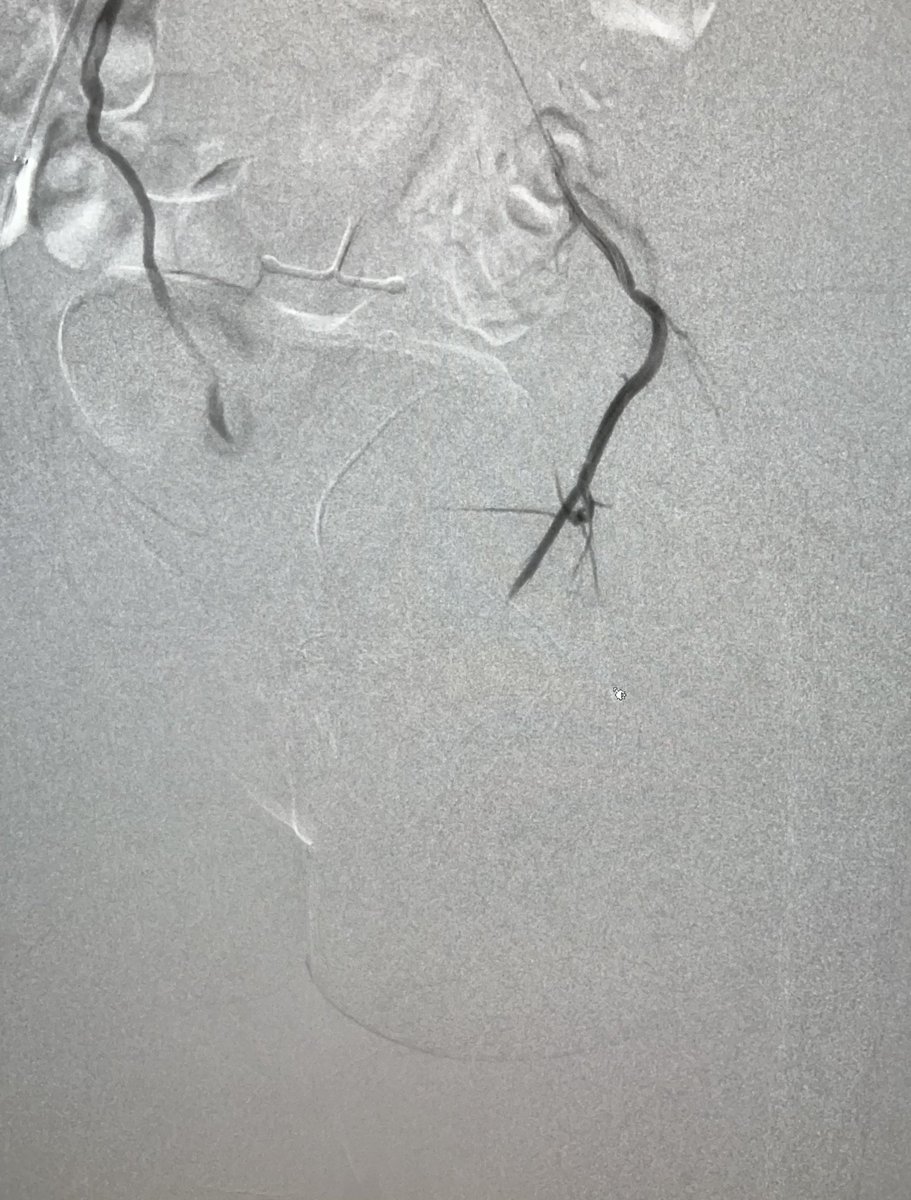

About 1/3 of our traumas involve the pelvis, here the left superior gluteal artery is bleeding from multiple branches. After embolization, hg stabilized and vitals improved.

0

2

20